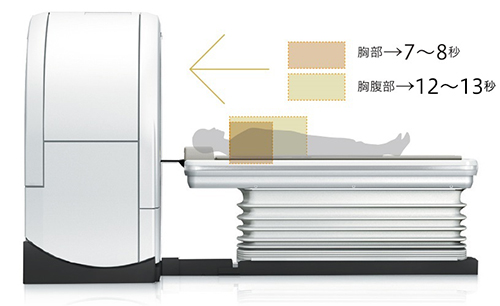

特長<2>

高スループットで撮影時の負担を軽減

高速回転,サブミリスライス撮影,パワフルな線量を生み出すジェネレータ,そして画像再構成アルゴリズム。高いパフォーマンスが高精細で高スループットな検査を実現します。

高精細・高画質を可能にする0.625mmサブミリ撮影

0.625mm×16chの撮影により,高精細な画像を短時間で撮影可能です。滑らかな3D画像,MPR画像も得られ,撮影後にはMPRによるオブリーク画像の作成も可能です。